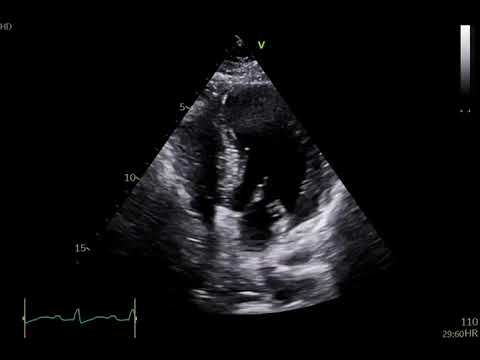

Four chamber view showing ejection fraction of 62% and resting tachycardia

Normal heart Ef=55-70% & Heart failure EF=25-30% Echo l #echo #shorts